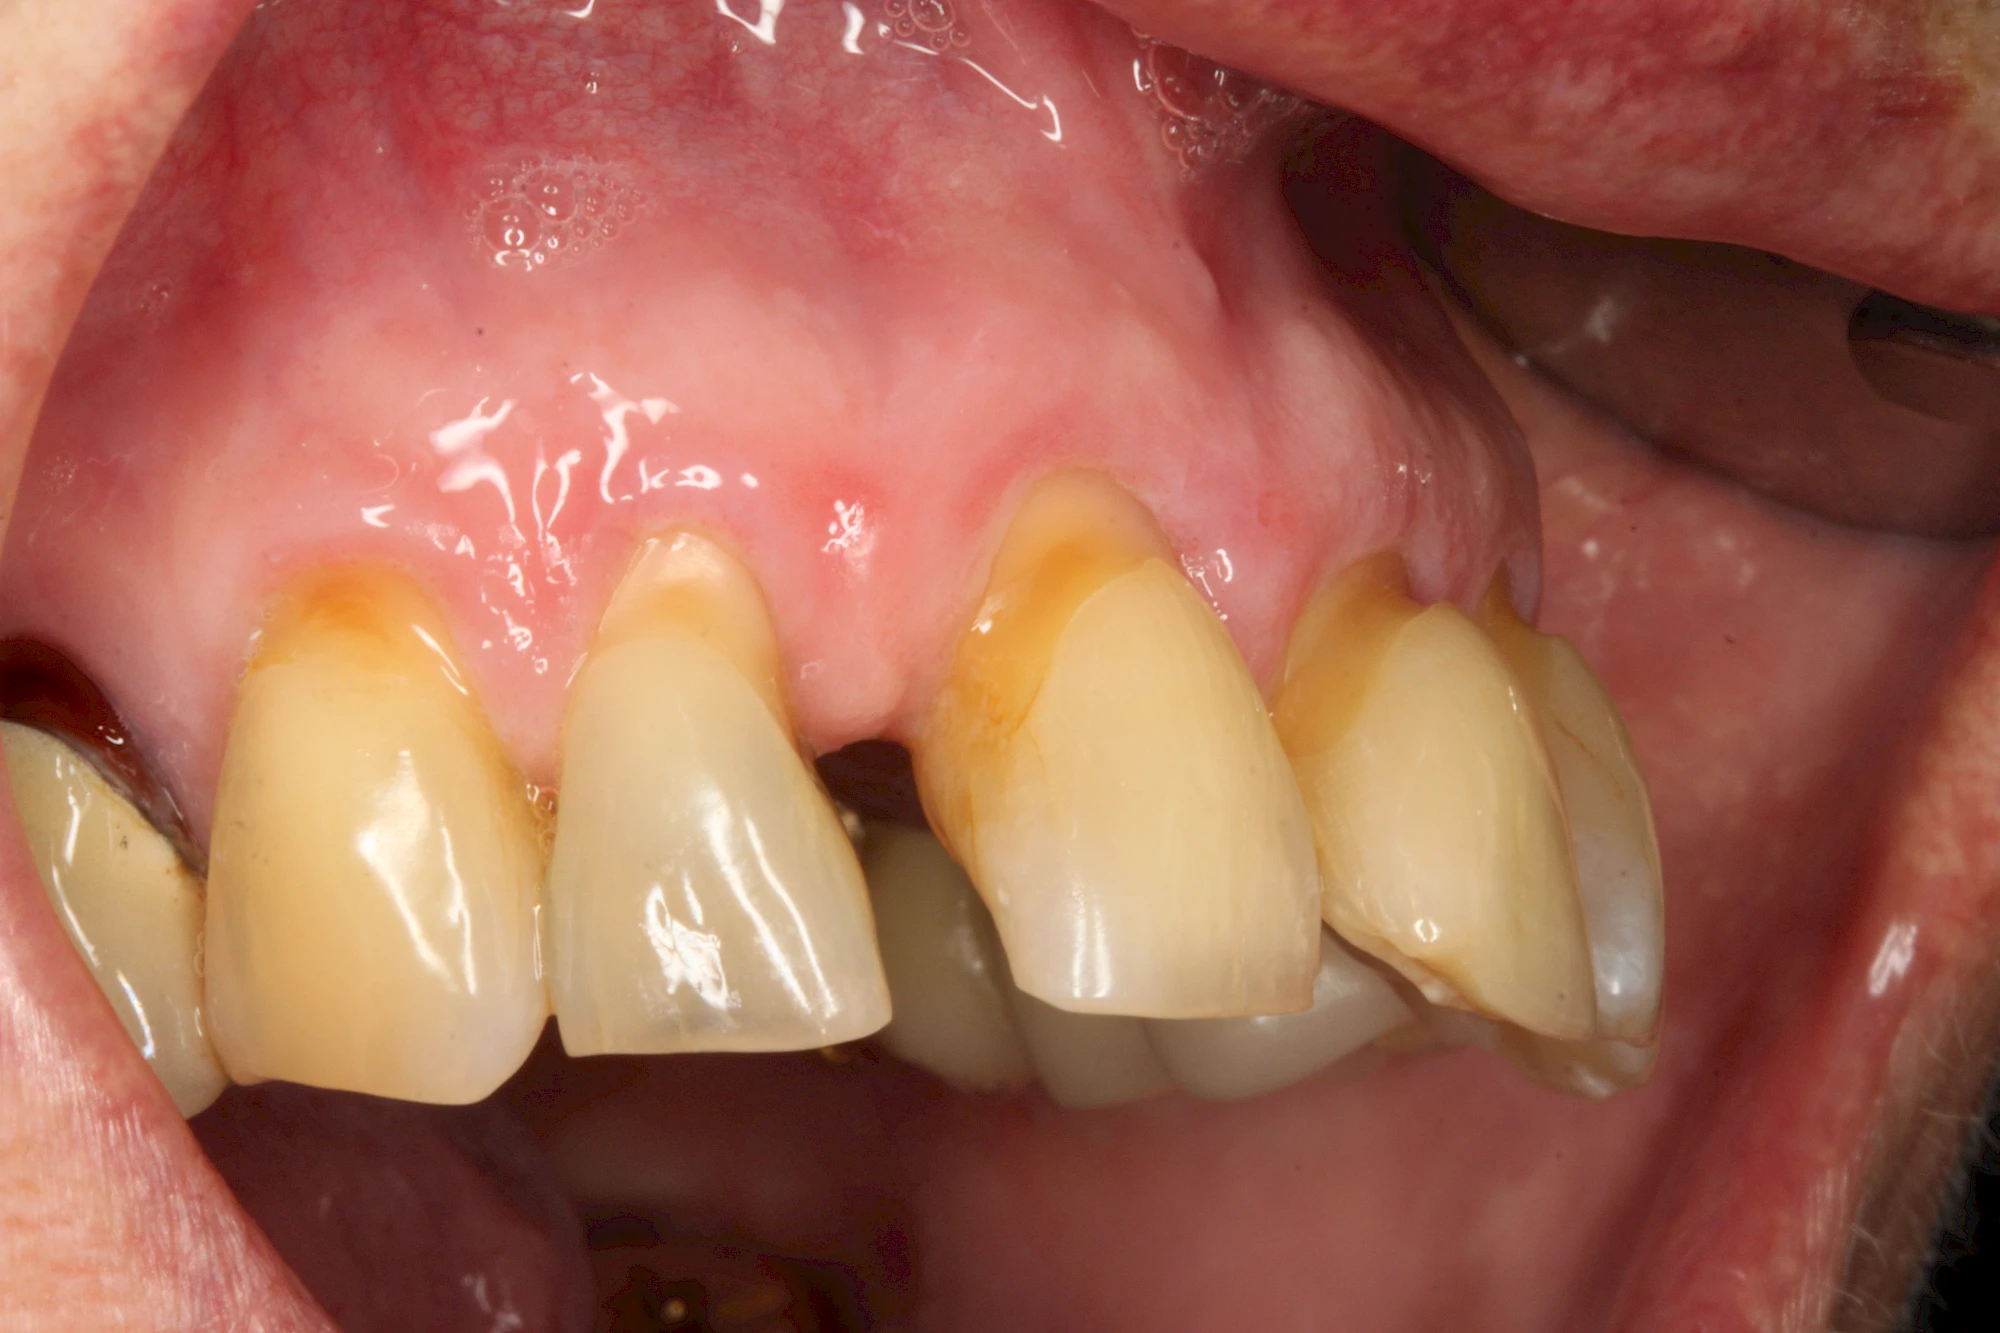

Auswaschung

Auswaschung (Erosion) dagegen ist eine Verschleißerscheinung der Zähne aufgrund von immer wiederkehrenden Säureangriffen durch die Nahrung, verstärkt zum Beispiel durch den Genuss säurehaltiger Getränke oder Speisen. Auch bei Menschen mit einer Essstörung (z. B. Bulimie) können die Zähne durch die Magensäure ausgewaschen erscheinen.